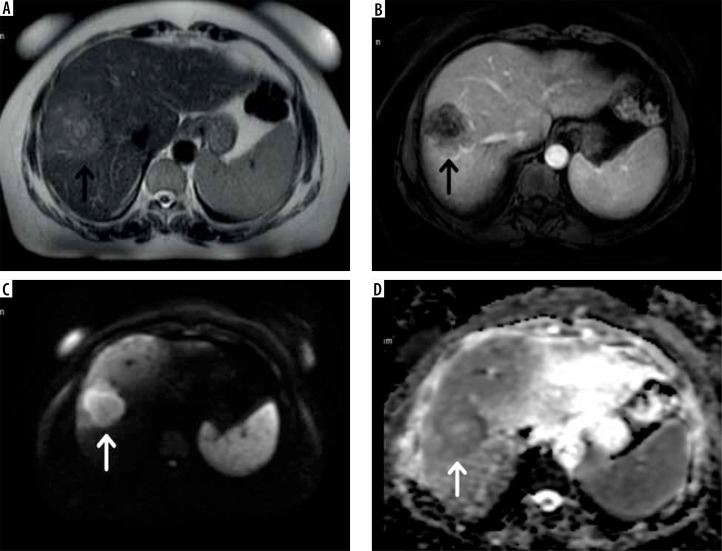

Material and methods: A total of 197 hepatic lesions were retrospectively analyzed across 3 different MRI sets: AMRI-1 (dynamic enhanced + T2W), AMRI-2 (DWI + T2W), and a standard MRI protocol. The patient cohort included 100 individuals (63 males, 37 females) with a mean age of 62.6 years (SD: 11.1 years). Lesions were characterized as benign, malignant, or indeterminate based on histopathology, positron emission tomography-computed tomography (PET-CT), and follow-up imaging.

Results: The standard MRI protocol identified 197 liver lesions (175 metastatic, 18 benign, and 4 indeterminate); 142 lesions (72.1%) were larger than 10 mm, with the majority being metastatic (140/142). Radiologist 1 identified 195 lesions using the AMRI-1 protocol (175 metastatic, 15 benign, and 5 indeterminate). The sensitivity per lesion was 89.7% (95% CI: 0.85-0.93). Radiologist 2 identified 183 lesions using the AMRI-2 protocol (169 metastatic, 6 benign, and 8 indeterminate). The sensitivity per lesion was 92.3% (95% CI: 0.88-0.95). No statistically significant difference was found in sensitivity between the AMRI-1 and AMRI-2 and standard MRI protocols (p > 0.05).

Conclusions: The standard MRI protocol demonstrated the highest sensitivity and specificity for detecting and characterizing liver metastases. However, differences between the protocols were not statistically significant. Abbreviated MRI protocols, particularly the AMRI-2 protocol incorporating diffusion-weighted imaging, could serve as an effective alternative for routine clinical practice.